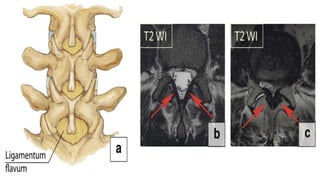

Ligamentum flavum hypertrophy

• It extends from the 2nd vertebra to the 1st sacral

vertebra, connecting the two adjacent laminae

• The ligamentum flavum tends to become

hypertrophic with the degeneration of the elastic

fibres and the proliferation of type II collagen.

• Abnormal motions and instability within the

involved segments are potential aetiologies of

ligamentum flavum hypertrophy as the body tries

to stabilise the diseased segment by making it

• Surgical removal is the only

therapeutic manoeuvre for

patients with symptoms caused

by ligamentum flavum

hypertrophy (Fig. 26b, c).

Ligamentum flavum hypertrophy •It extends from the 2nd vertebra to the 1st sacral vertebra, connecting the two adjacent laminae • The ligamentum flavum tends to become hypertrophic with the degeneration of the elastic fibres and the proliferation of type II collagen. • Abnormal motions and instability within the involved segments are potential aetiologies of ligamentum flavum hypertrophy as the body tries to stabilise the diseased segment by making it

• 31.

• Surgical removalis the only therapeutic manoeuvre for patients with symptoms caused by ligamentum flavum hypertrophy (Fig. 26b, c).